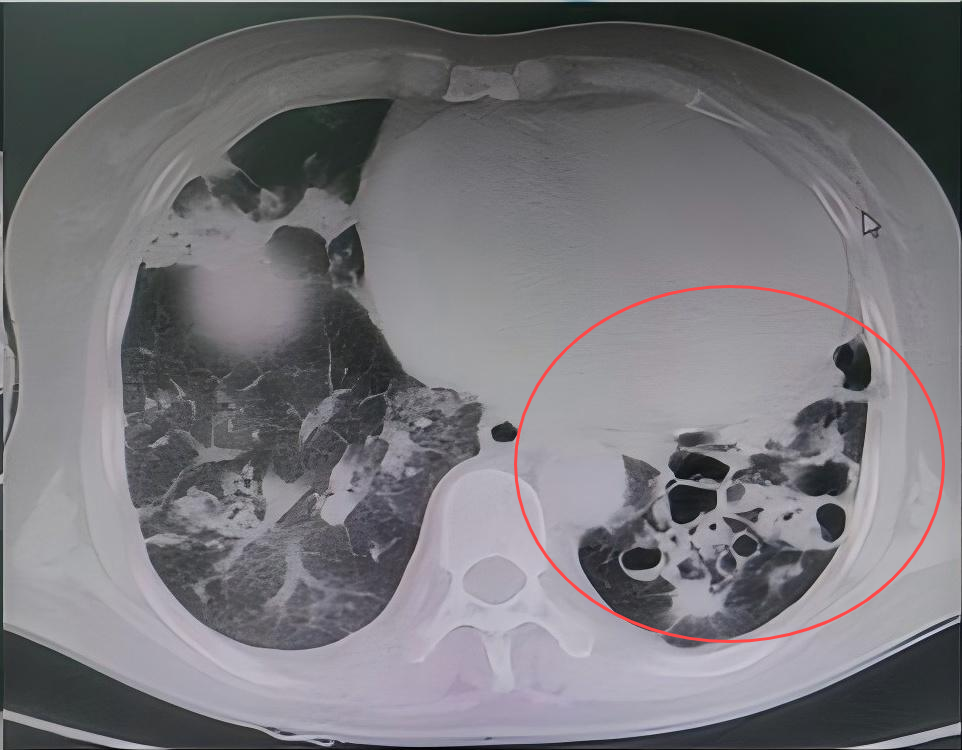

患者郑某某,因支气管扩张、空洞反复咯血十余年,再次复发后,咯血量明显增多,在当地治疗一周因效果不佳转入我院,就诊于急诊时仍咯血200ml,呼吸与危重症医学科立即启动绿色通道将患者送入介入室手术,术中仍持续咯血,在实施支气管动脉栓塞术后,患者咯血立即停止。在呼吸与危重症医学科医护人员的精心治疗下,患者最终好转出院,至今无复发。

CT提示患者双肺大片病灶,支气管扩张,空洞。

病 灶

空 洞

支气管扩张